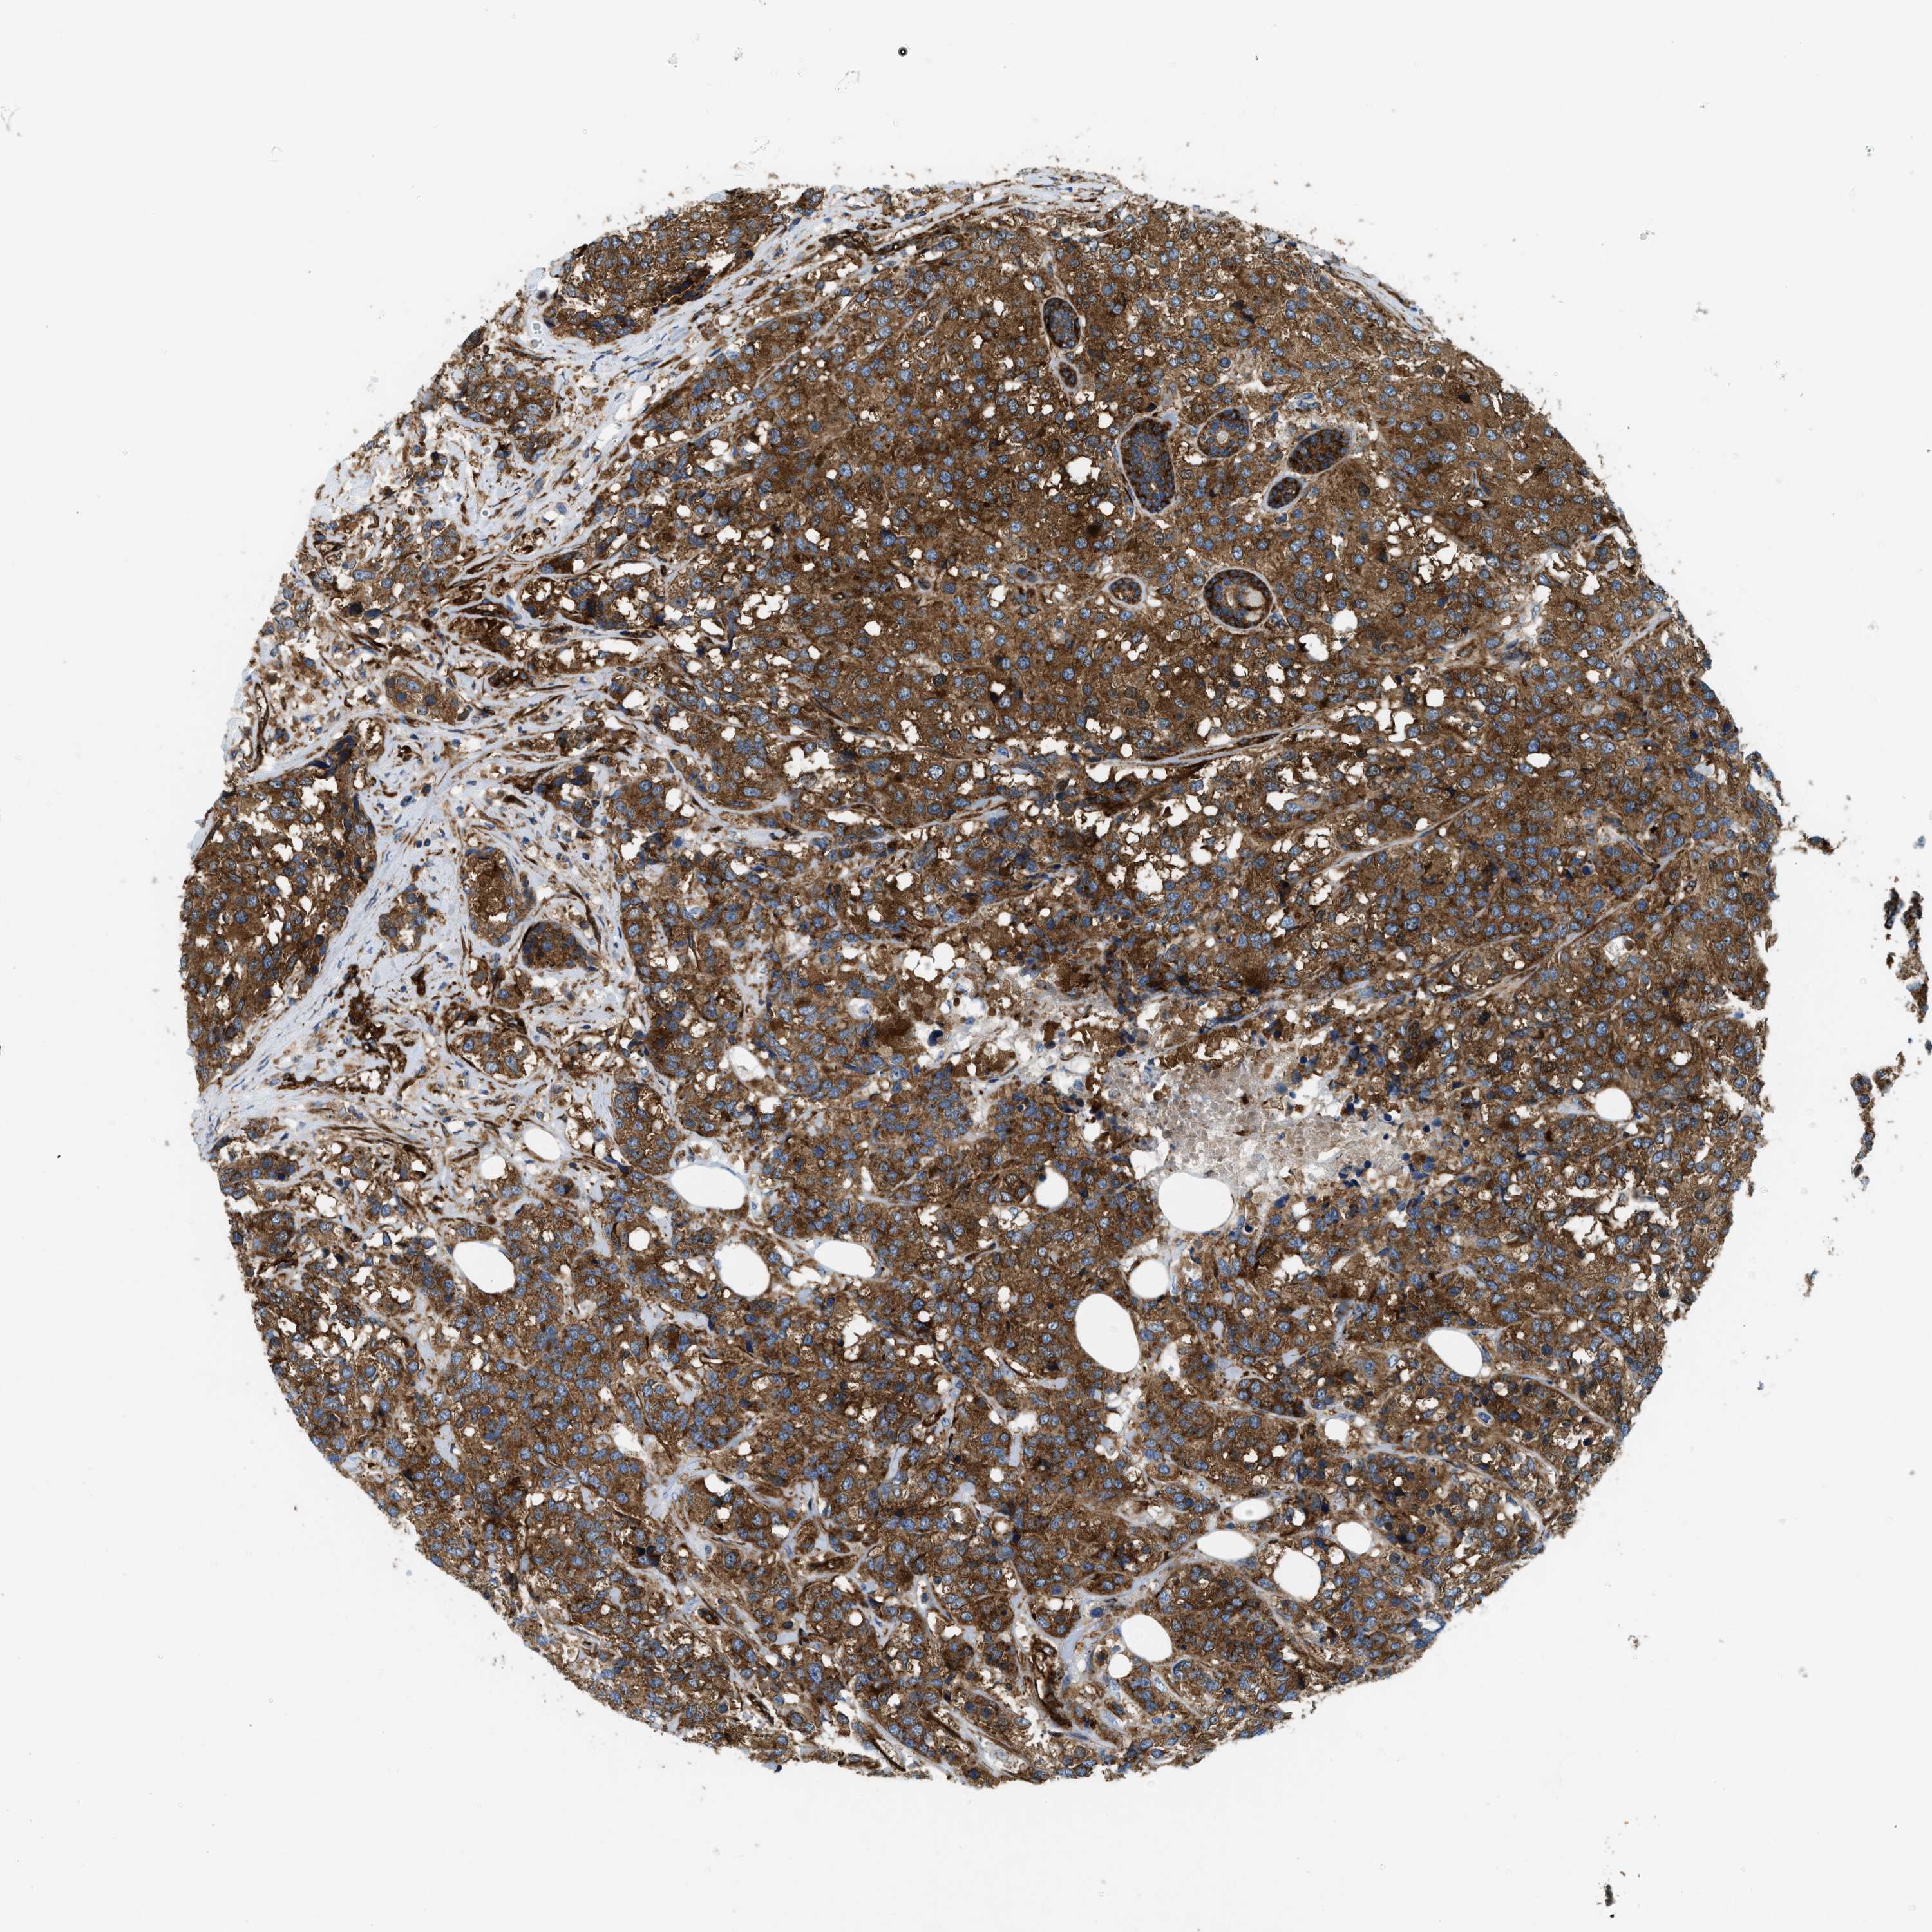

CANCER BREAST CANCER Show tissue menu

BRCA TCGA BRCA VALIDATION PROTEIN EXPRESSION